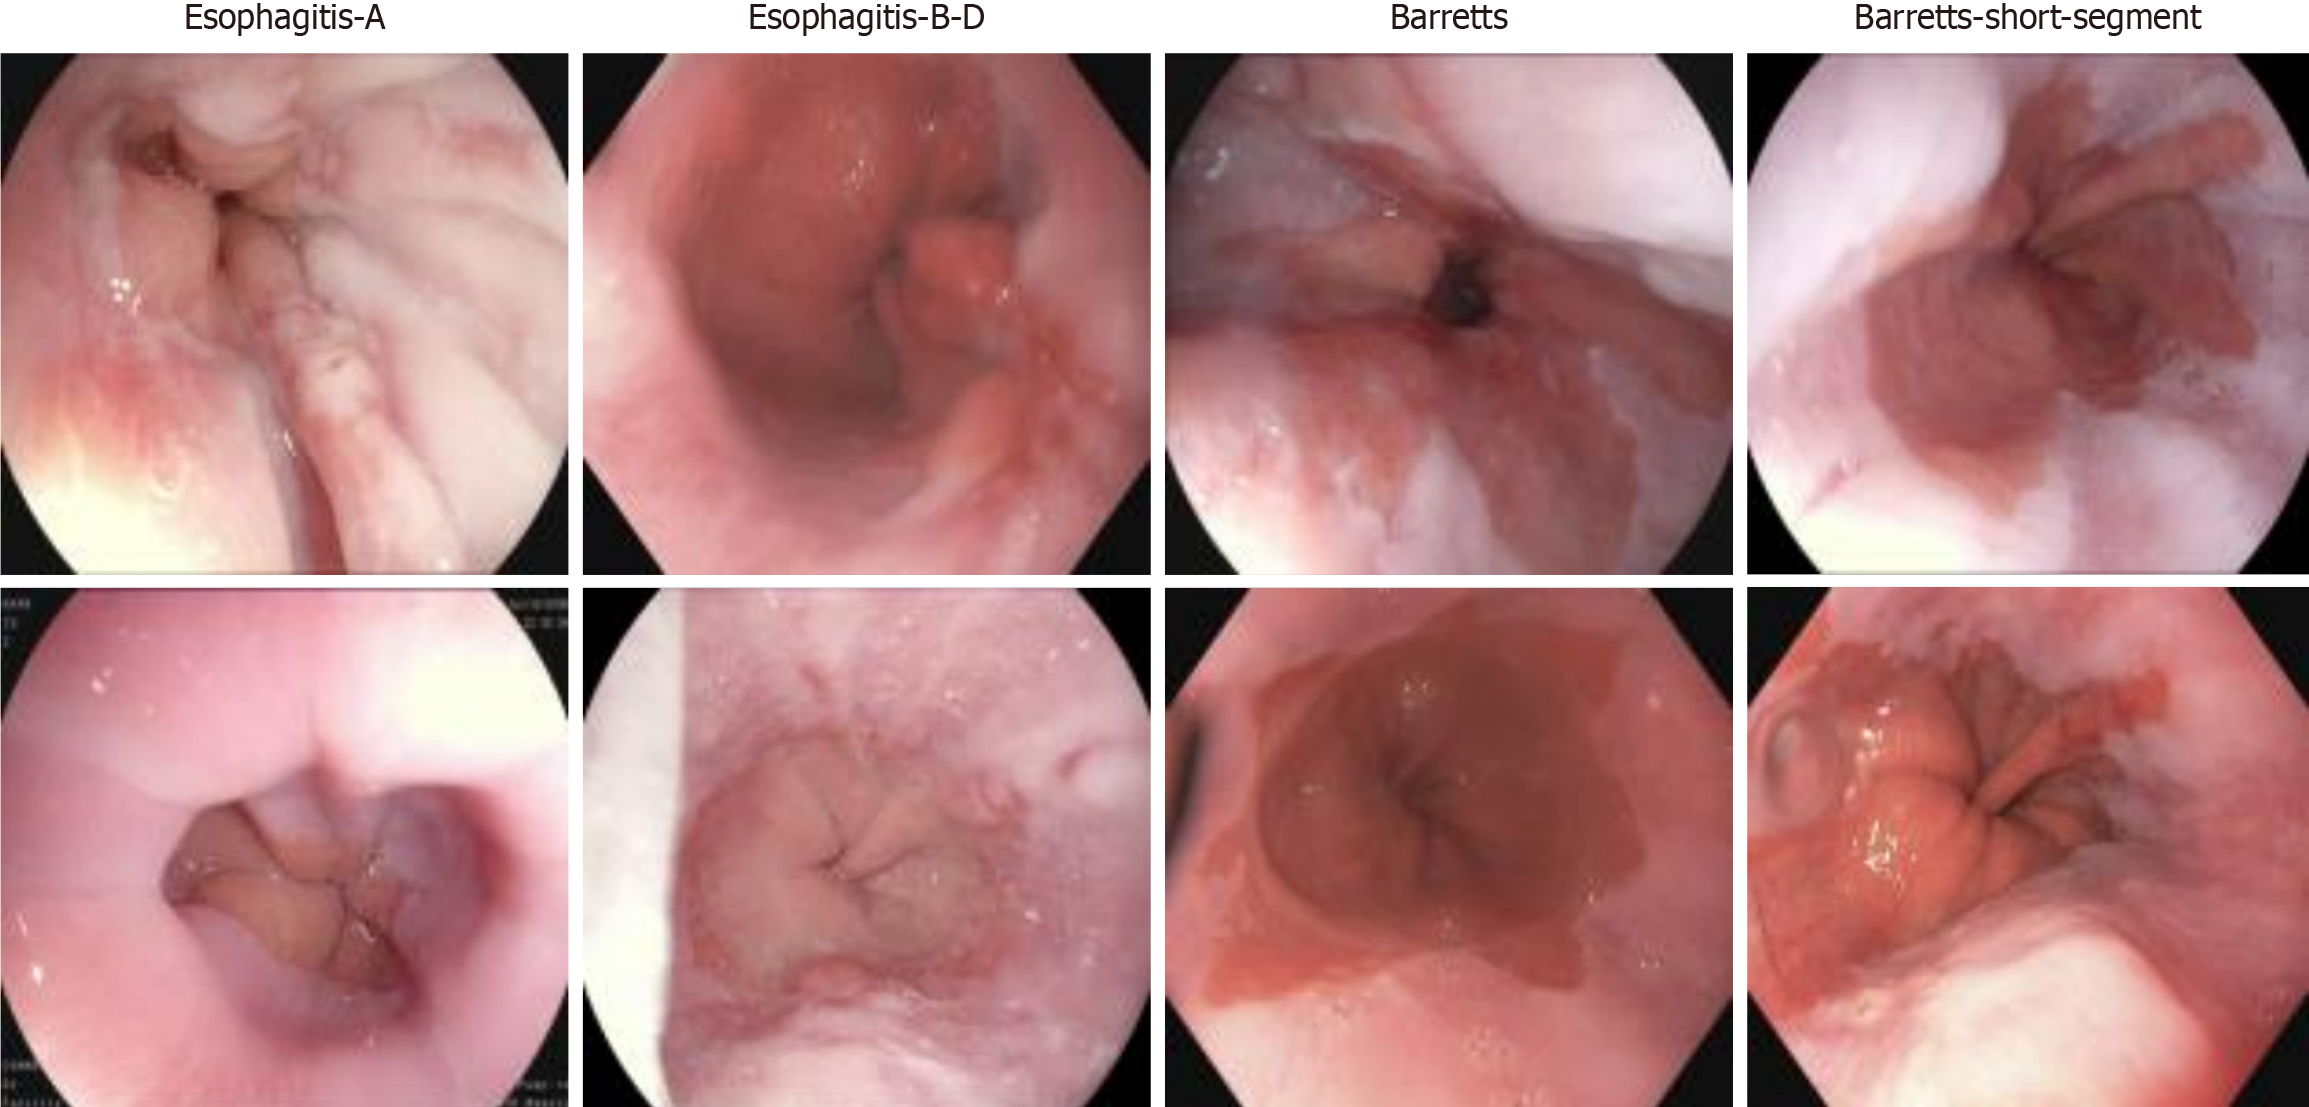

Additionally, the Hyper Kvasir dataset consists of images annotated and validated by experienced endoscopists, covering various categories, including anatomical landmarks, pathological findings, and endoscopic procedures within the gastrointestinal tract. Each category contains hundreds of images. For this study, we utilized a subset of this dataset, which includes images categorized as esophagitis types A and B-D, short-segment Barrett’s esophagus, and Barrett’s esophagus, with representative images shown in Figure 1. As part of the dataset preprocessing, the research team performed data cleaning before publication, removing low-quality or blurry images to ensure high dataset quality. These images have varying resolutions, ranging from 720 × 576 to 1920 × 1072 pixels, and are organized into separate folders named according to their contents. This study primarily focuses on the reflux esophagitis and Barrett’s esophagus subsets of the dataset.